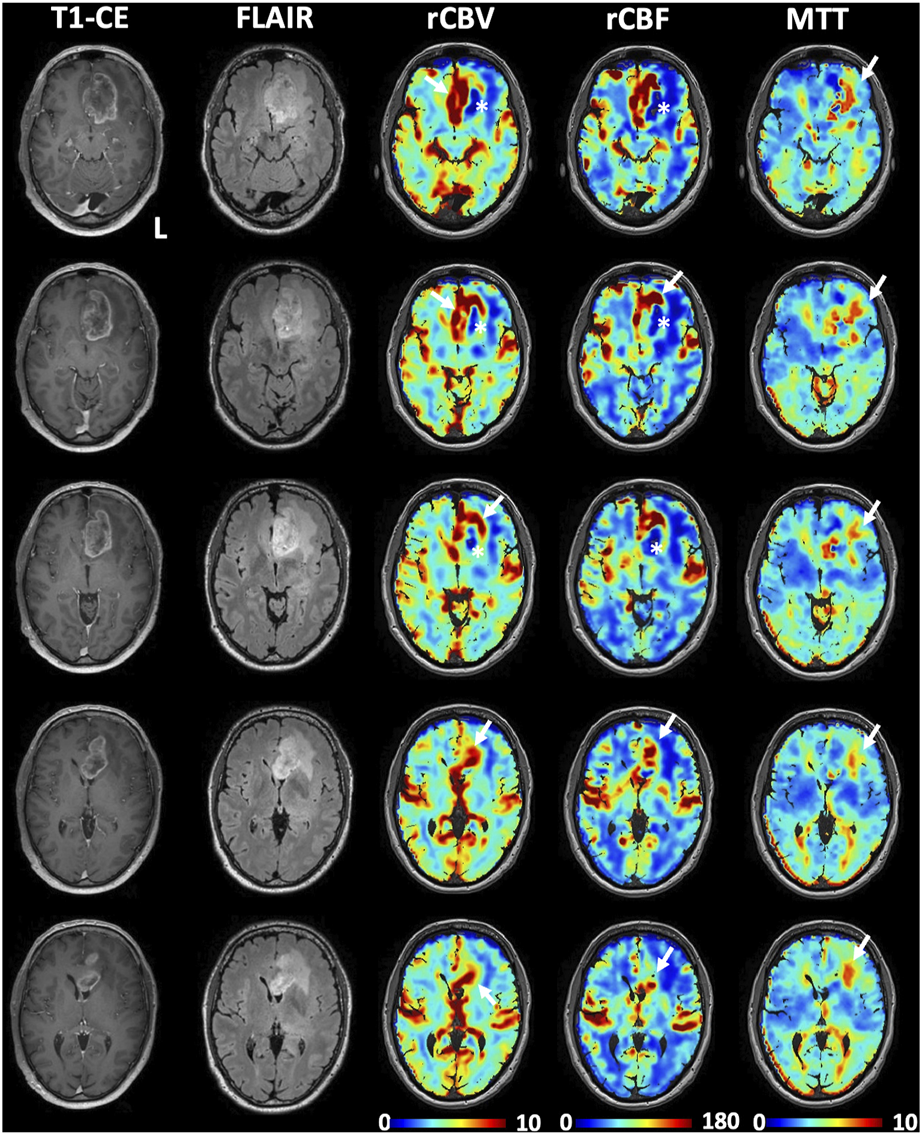

FIGURE 2

Illustrative perfusion maps obtained with the transient hypoxia induced-dOHb protocol during BOLD-MRI acquisition in a patient with left frontal glioblastoma. High perfusion, as represented by increased CBV and CBF, can be observed in correspondence of the contrast-enhancing lesion (white arrows), while decreased rCBV and rCBF can be observed in the central necrotic area (white asterisks) as well as the in the FLAIR hyperintensity typical of perilesional edema. Note that only a partial correspondence of increased perfusion is observed at the posterolateral margin of the contrast-enhancing lesion. High MTT values can be observed mostly in the perilesional edema (white arrows in the MTT maps).